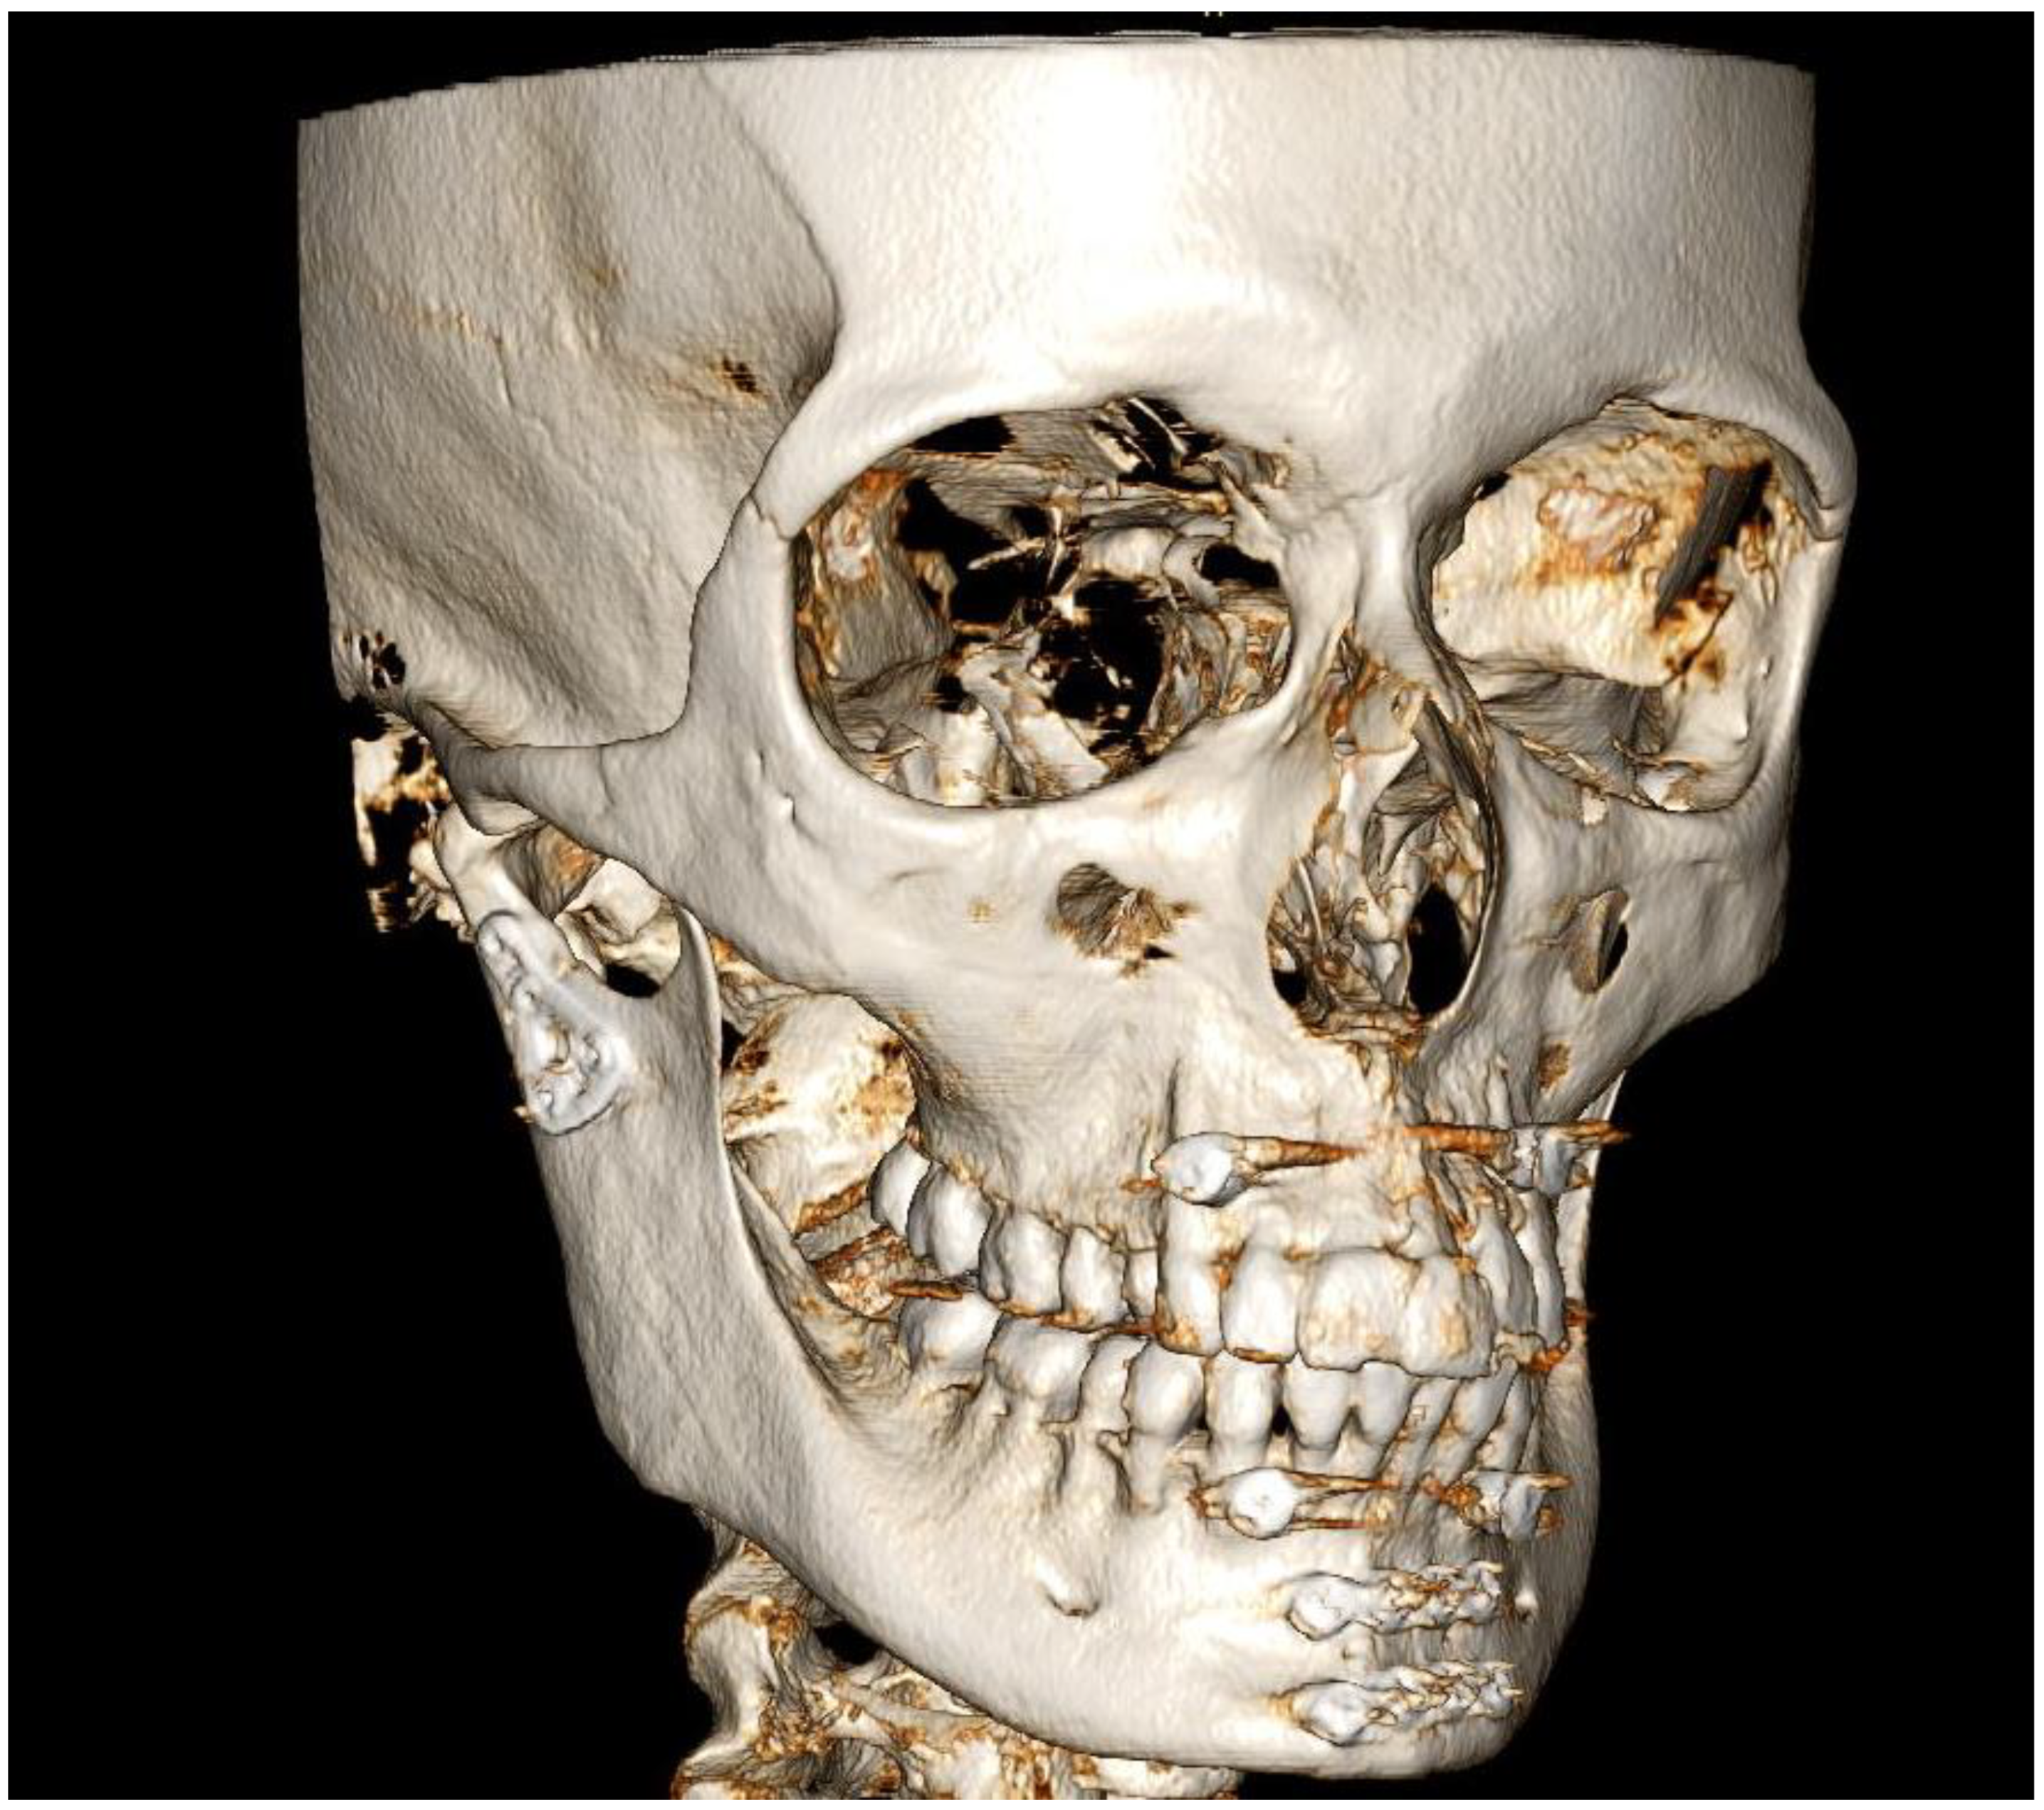

3.1. Case 1